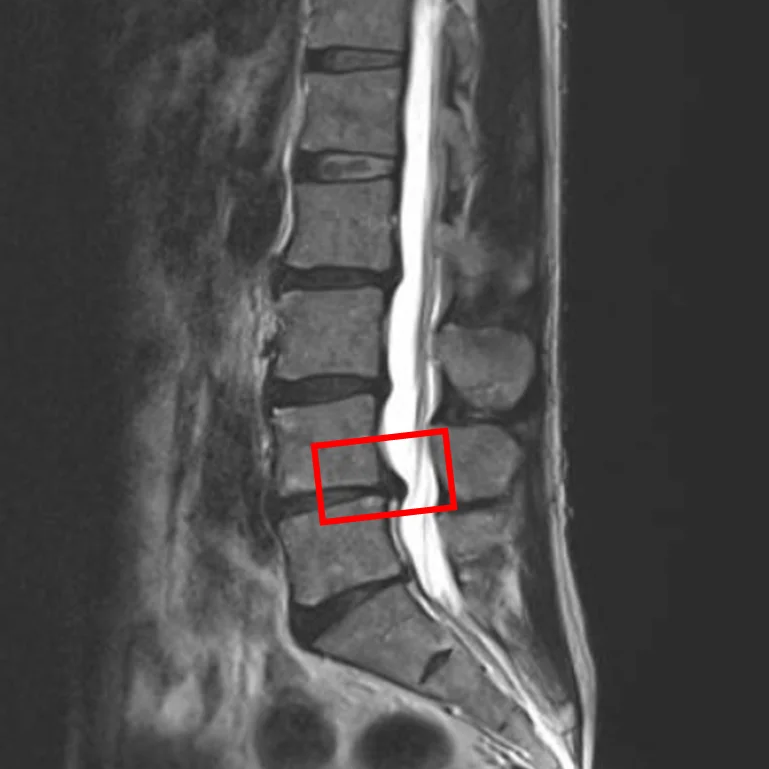

По данным МРТ и результатам осмотра пациента выявлена межпозвоночная грыжа диска L4/L5, дегенерация межпозвоночных дисков L2/L3, L3/L4 и L5/S1.

Симптомы по 10-балльной шкале (0 – отсутствие симптомов, 10 – сильные боли/онемение):

– боли в пояснице: 3;

– боли в ногах: 1;

– онемение в ногах: 2;

– боли в ягодицах: 2.